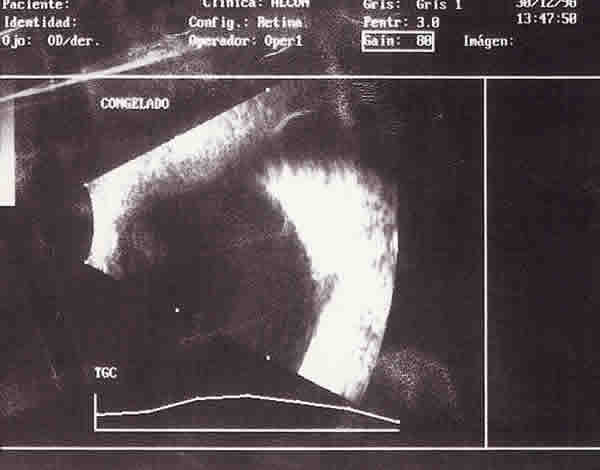

Figura 5

ECOGRAFÍA B DEL OJO IZQUIERDO. MUESTRA UNA PROFUNDA EXCAVACIÓN DEL DISCO ÓPTICO CON UNA REGIÓN ECODENSA EN LA BASE DE LA EXCAVACIÓN.